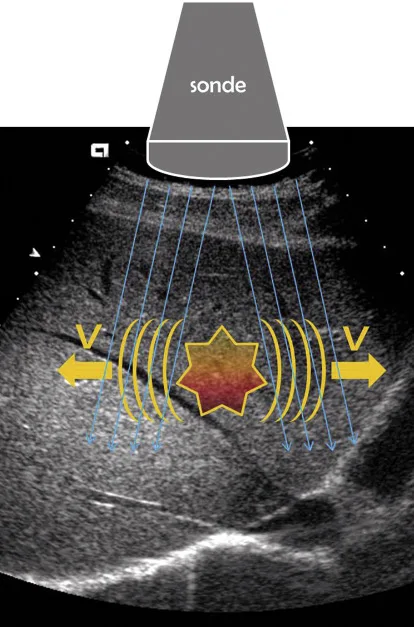

Quelle que soit la technique utilisée, le principe de l’élastométrie ultrasonore est toujours le même. Il consiste en la mesure de la vitesse de déplacement d’une onde de cisaillement créée dans le parenchyme hépatique. La vitesse de déplacement de cette onde est proportionnelle à la dureté du parenchyme. Pour le Fibroscan la technique de création de l’onde est mécanique. Un impact est provoqué sur la paroi cutanée dans un espace intercostal, créant une onde de cisaillement qui se propage de la peau vers la profondeur du foie. Pour les modules associés à des échographes, la génération de l’onde de cisaillement se fait par une onde ultrasonore à haut impact mécanique. En effet les ultrasons, en fonction de leur fréquence, ont une pénétration plus ou moins grande dans les structures (les ultrasons à basse fréquence peuvent pénétrer très loin, c’est le principe des sonars utilisés en milieu marin) et un impact mécanique différent (en focalisant des ultrasons à basse fréquence, on obtient un impact mécanique important ; c’est le principe des destructions de calculs urinaires par lithotritie). Cette onde de compression va générer une onde de cisaillement (perpendiculairement à l’onde de compression). Quel que soit le système, la mesure de la vitesse de propagation de l’onde de cisaillement est ensuite faite par des tirs d’ultrasons répétés. La mesure peut être ponctuelle ou intéresser un volume limité comme dans la technique ARFI de Siemens où la fenêtre de mesure est de 10 × 5 mm, ou dans une fenêtre plus large en utilisant des techniques de génération et de mesure de vitesse de l’onde de cisaillement plus sophistiquées, comme la technique utilisée par Supersonic Imagine (SSI) qui permet dans une plus large fenêtre d’obtenir une cartographie couleur de la dureté hépatique, et une mesure quantitative de la dureté dans une région d’intérêt. [1]

Figure 1. Principe de mesure de l’élasticité hépatique par les techniques ARFFI et SSI. Une onde de compression créait une onde de cisaillement. L’onde de cisaillement se propage perpendiculairement à l’onde de compression. La vitesse de propagation est mesurée par des tirs ultrasonores. La vitesse de propagation de l’onde de cisaillement est proportionnelle à la dureté (l’élasticité) hépatique.